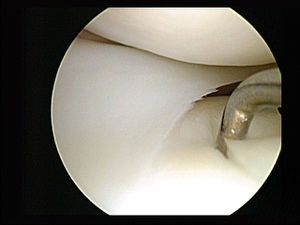

إن الإجراءات طفيفة التوغل تشمل بالعادة استخدام التنظير المفصلي ( للمفاصل والعمود الفقري) أو جهاز منظار البطن والتحكم عن بعد باستخدام آلات محددة مع المراقبة غير المباشرة في مجال العملية عن طريق المنظار الداخلي أو على نطاق كبير من خلال شاشة العرض، ويتم ذلك من خلال الجلد أو من خلال تجويف الجسم أو الفُتح التشريحية. كما انه تُقدم الأشعة التداخلية العديد من التقنيات التي تجنب الحاجة لإجراء عملية جراحية.[5]

هناك العديد من الإجراءات الطبية التي تندرج تحت مسمى طفيفة التوغل؛ تلك التي تنطوي على شقوق صغيرة والتي يدخل من خلالها المنظار الداخلي، حيث انه يميزها لاحقة في نهاية الكلمة وهي "- سكوب "، مثال على ذلك الإندوسكوب أو (التنظير الداخلي)، اللابروسكوب أو (التنظير البطني)، الأرثروسكوب أو (التنظير المفصلي). ومن الأمثلة الأخرى على إجراءات طفيفة التوغل هي استخدام حقن تحت الجلد، حقن ضغط الهواء، الزراعة تحت الجلد، الجراحة الانكسارية، الجراحة عن طريق الجلد، الابتراد الهوائي، الجراحة الميكروسكوبية، جراحة ثقب المفتاح، جراحة الأوعية الدموية باستخدام الأشعة التداخلية (مثل تقنية رأب الوعاء)، القسطرة التاجية، أقطاب دائمة التنسيب في العمود الفقري والدماغ، الجراحة التجسيمية، إجراء نوس، أساليب التصوير الطبي القائم على النشاط الإشعاعي، مثل كاميرا گاما، التصوير المقطعي بالإصدار البوزيتروني والتصوير الطبي باستخدام أشعة گاما. أما الإجراءات المتعلقة فهي الجراحة بالصور الموجهة، والجراحة الروبوتية [6] وأنواع اخرى من التصوير الإشعاعي.